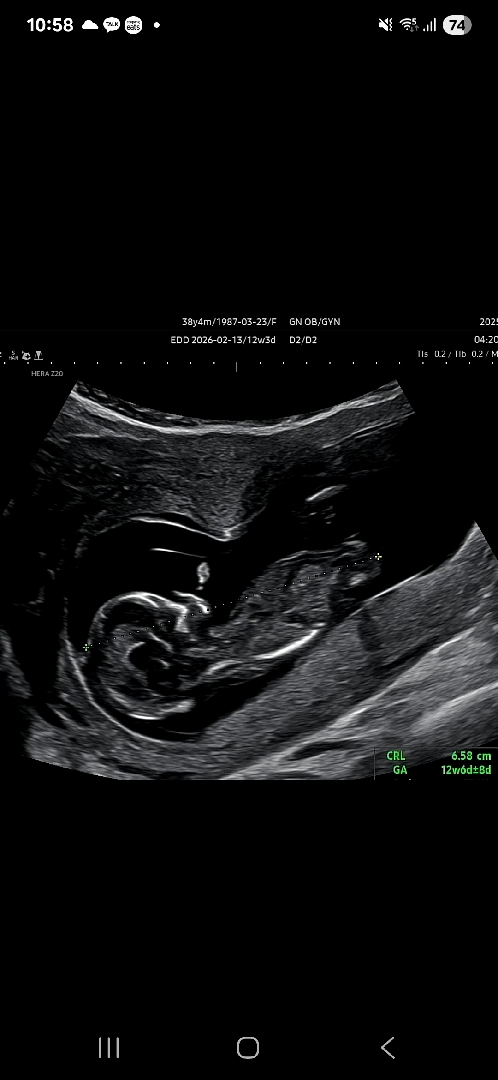

성별?

이거루 성별보이나유?

딸이네요 ㅎㅎ